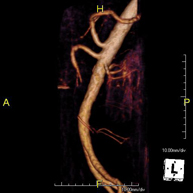

Prueba diagnóstica no invasiva que consiste en el estudio de la arteria aorta abdominal, obteniendo imágenes de alta definición anatómica mediante el empleo de un campo electromagnético y ondas de radio (con un emisor y un receptor). Es indispensable el uso de contraste paramagnético (Gadolinio). Sin embargo, no utiliza radiación ionizante. La calidad de las imágenes permite realizar reconstrucciones en 2D y 3D. Está indicado en aquellos pacientes con enfermedad vascular (aterosclerosis), estudio de aneurismas, en estudios pre-quirúrgicos de lesiones adyacentes a la aorta abdominal como "mapa" vascular, etc. - Angio RM Aorta-ilíaca

Prueba diagnóstica no invasiva que consiste en el estudio de la arteria aorta abdominal de las arterias ilíacas, obteniendo imágenes de alta definición anatómica mediante el empleo de un campo electromagnético y ondas de radio (con un emisor y un receptor). Es indispensable el uso de contraste paramagnético (Gadolinio). Sin embargo, no utiliza radiación ionizante. La calidad de las imágenes permite realizar reconstrucciones en 2D y 3D. Esta prueba está especialmente indicada como estudio pre-quirúrgico (mapa vascular) antes de intervenciones percutáneas o quirúrgicas de aorta abdominal y arterias ilíacas, estudio complementario en pacientes con isquemia de miembros inferiores, etc. - Angio RM Arterial extremidades inferiores

Prueba diagnóstica no invasiva que consiste en el estudio vascular del sector aorto-ilíaco y de los vasos arteriales de ambas extremidades inferiores, obteniendo imágenes de alta definición anatómica mediante el empleo de un campo electromagnético y ondas de radio (con un emisor y un receptor). Es indispensable el uso de contraste paramagnético (Gadolinio). Sin embargo, no utiliza radiación ionizante. La calidad de las imágenes permite realizar reconstrucciones en 2D y 3D. Está especialmente indicado en aquellos pacientes en los que hay sospecha de enfermedad vascular de ambas extremidades, en pacientes con enfermedad vascular de ambas extremidades como el mapa vascular antes del tratamiento (percutáneo o quirúrgico), como el mapa vascular pre-quirúrgico en pacientes con lesiones óseas o musculares que requieran cirugía, etc. - Angio-RM Arterias renales